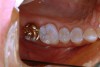

Figure 7 demonstrates a quadrant of old amalgam restorations present on a 32-year-old patient. Clinically, teeth Nos. 2 and 3 tested positive for cuspal fracture. Teeth Nos. 3 through 5 had radiographic evidence of recurrent decay. Each of these teeth had numerous treatment options. A case could be made for all four posterior teeth to be restored with crowns, and this certainly was one treatment option. However, with this young patient every effort was made to minimize the loss of tooth structure while still providing the functional restoration required to provide protection of the tooth and return each tooth to proper health and function while meeting the patient’s esthetic requests.

Figure 7   Preoperative view of a quadrant of failing amalgams.

Figure 7